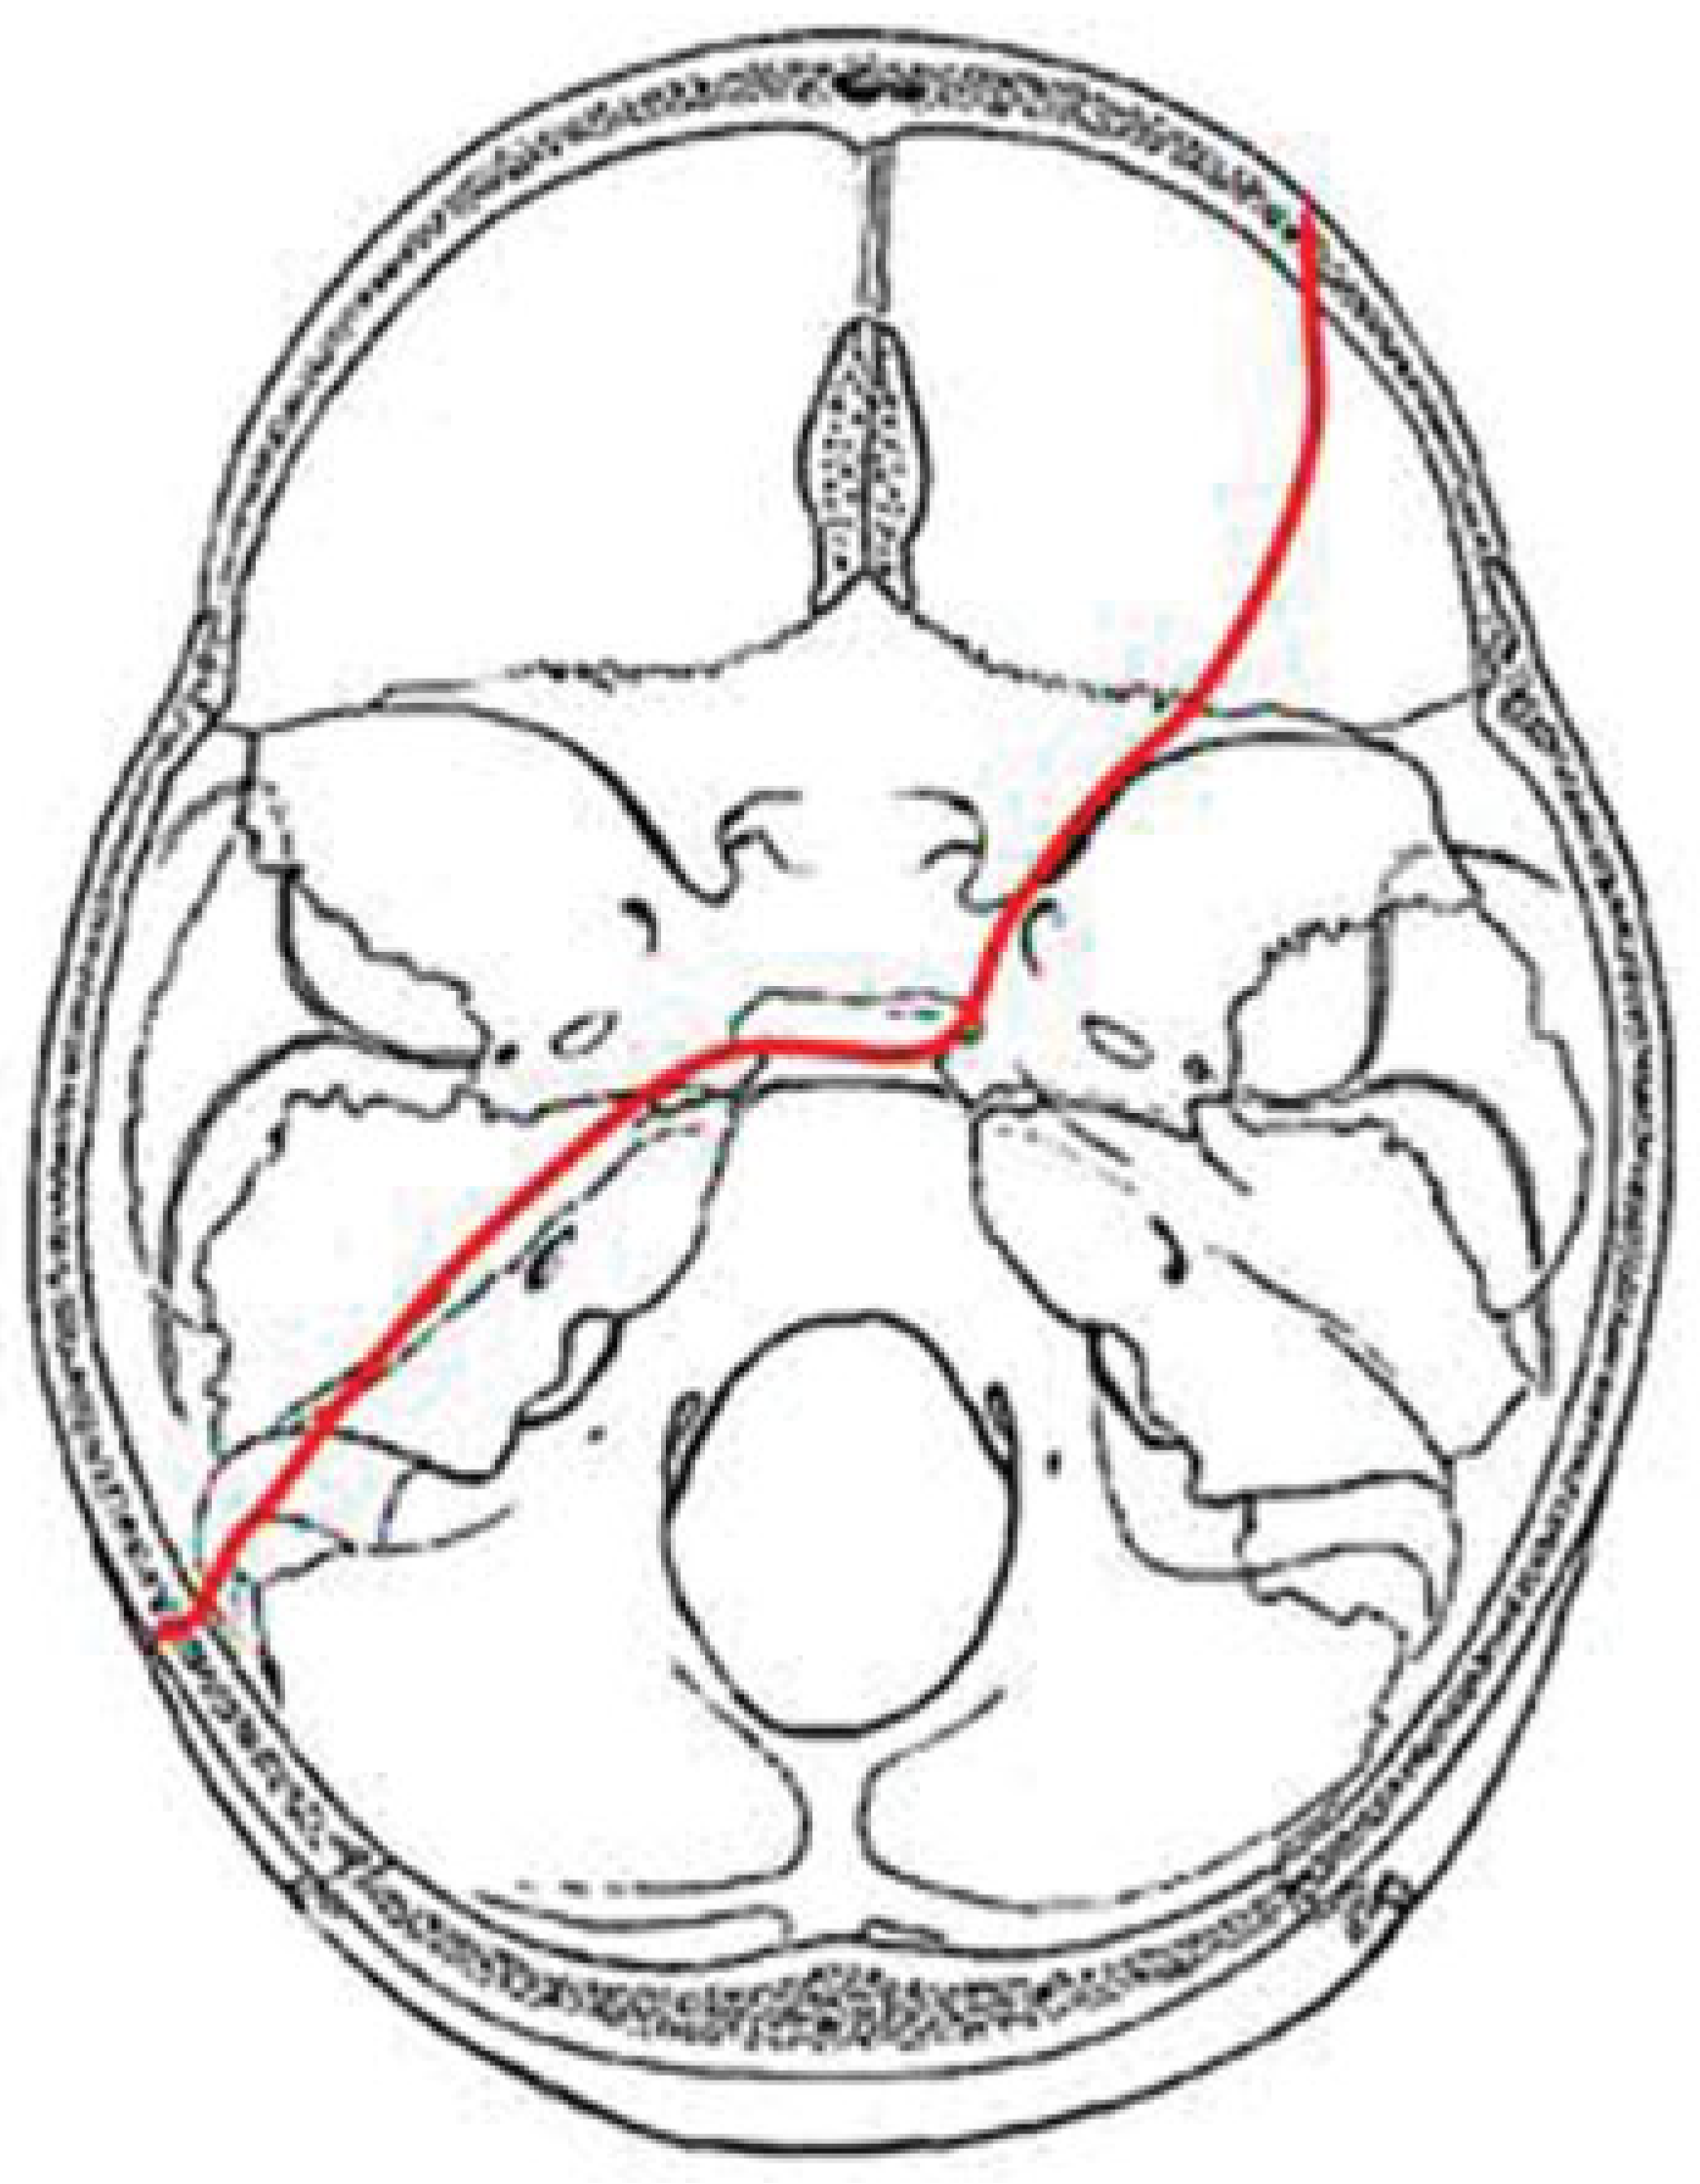

In our study we identified four major fracture patterns of transsphenoidal basilar skull fractures, which were: anterior transverse (AT), lateral frontal diagonal (LFD), posterior trans-verse (PT), and mastoid diagonal (MD), which matches Clark’s descriptions of the transsphenoidal basilar skull fractures.17

MD Pattern

These fractures occur in patients with mastoid impact and who had diagonal fractures extending from the ipsilateral occipital bone at the occipitomastoid suture across the jugular foramen to the petro-occipital fissure and into the sphenoid body. The fractures cross the sphenoid sinus diagonally and exit it anteriorly across the sphenoidal plane. There are ipsilateral temporal bone fractures with associated diastasis of the ipsilateral sphenopetrosal sincondrosis. The MD frac-ture crosses the sphenoid body diagonally from posterior to anterior. Also the MD fracture terminates in the contralateral anterior cranial fossa (Figure 8).

Figure 8. Composite drawing of the mastoid diagonal pattern (left impact).